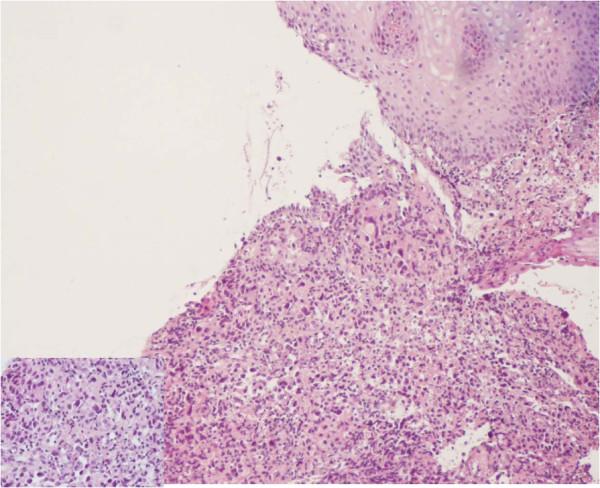

A 56 year-old non smoking woman, with no alcohol intake and no familial history of cancer; followed in the National Institute of Oncology of Rabat Morocco since 1999 for breast carcinoma, presented on consultation on January 2011 with dysphagia. Breast cancer was treated with modified radical mastectomy, 6 courses of chemotherapy based on CMF regimen and radiotherapy to breast, inner mammary chain and to pelvis as castration. Less than a year later, a renal right mass was discovered incidentally. Enlarged nephrectomy realized and showed renal cell carcinoma. A local and metastatic breast cancer recurrence occurred in 2007. Patient had 2 lines of chemotherapy and 2 lines of hormonotherapy with Letrozole and Tamoxifen assuring a stable disease. On January 2011, the patient presented dysphagia. Oesogastric endoscopy showed middle esophagus stenosing mass. Biopsy revealed adenocarcinoma. No evidence of metastasis was noticed on computed tomography and breast disease was controlled. Palliative brachytherapy to esophagus was delivered. Patient presented dysphagia due to progressive disease 4 months later. Jejunostomy was proposed but the patient refused any treatment. She died on July 2011.

一名56岁不吸烟女性,无饮酒史且无癌症家族史;自1999年起在摩洛哥拉巴特国家肿瘤研究所因乳腺癌接受随访,2011年1月因吞咽困难前来就诊。乳腺癌采用改良根治性乳房切除术、基于CMF方案的6个疗程化疗以及对乳房、内乳链和盆腔进行放疗作为去势治疗。不到一年后,偶然发现右肾肿物。实施扩大肾切除术,结果显示为肾细胞癌。2007年发生局部和转移性乳腺癌复发。患者接受了2线化疗和2线激素治疗,使用来曲唑和他莫昔芬,病情稳定。2011年1月,患者出现吞咽困难。食管胃内镜检查显示食管中段有狭窄肿物。活检显示为腺癌。计算机断层扫描未发现转移迹象,乳腺疾病得到控制。对食管进行了姑息性近距离放疗。4个月后,患者因病情进展出现吞咽困难。建议行空肠造口术,但患者拒绝任何治疗。她于2011年7月去世。